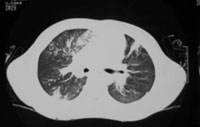

胸部CT(1):入院7天(病程67天) 胸部CT(2):入院7天(病程67天) (双肺多发点片状高密度影,右下肺背段可见致密团块影,外缘贴近胸壁,左上中肺内见一圆形病灶,中空,双肺门影增浓,心影增大,左室为主,纵隔内未见肿大淋巴结影)

任甄华 主治医师(放射科):X线胸片对于提示肺栓塞有重要参考价值,单纯肺栓塞胸片可能有五种表现:(1)缺血性改变:局部血管纹理减少,即Westermark征;(2)肺血管大小的改变;(3)心脏变化;(4)肺体积缩小;(5)胸膜渗出。值得强调的是,感染性心内膜炎引起的肺栓塞影像学改变与其他病因引起者不同,典型表现为散在、双侧的外周结节与不同程度的肺空洞性损害,损害呈圆形或楔形,多发生在下肺的外侧部分。本病例就体现了这一特点(见附图),这可能与栓子较小且携带病原菌,造成栓塞部位的继发感染有关。

但必须指出,肺栓塞的X线胸片表现多种多样,呈典型锥形改变的非常少见,部分肺栓塞的胸片可看不见任何异常表现。相当一部分胸片呈肺浸润表现,与肺炎相似。可从以下两点加以区别:①肺部一侧病变吸收,而另一侧出现新阴影的多发病变;②片影吸收呈“溶化征”,而肺炎吸收中片影出现密度不均现象,由此可见,在诊断中胸片的动态观察更为重要。有以上表现者应高度怀疑肺栓塞,再结合患儿是否存在高危因素,临床可做出正确诊断。切勿仅凭胸片轻易排除肺栓塞。本例患儿存在感染性心内膜炎、三尖瓣赘生物的基础病变,2个月病程中肺部阴影变化了3次,每次均为原有病灶吸收,在不同部位又出现了新的浸润影,结合临床表现,肺栓塞可确诊。